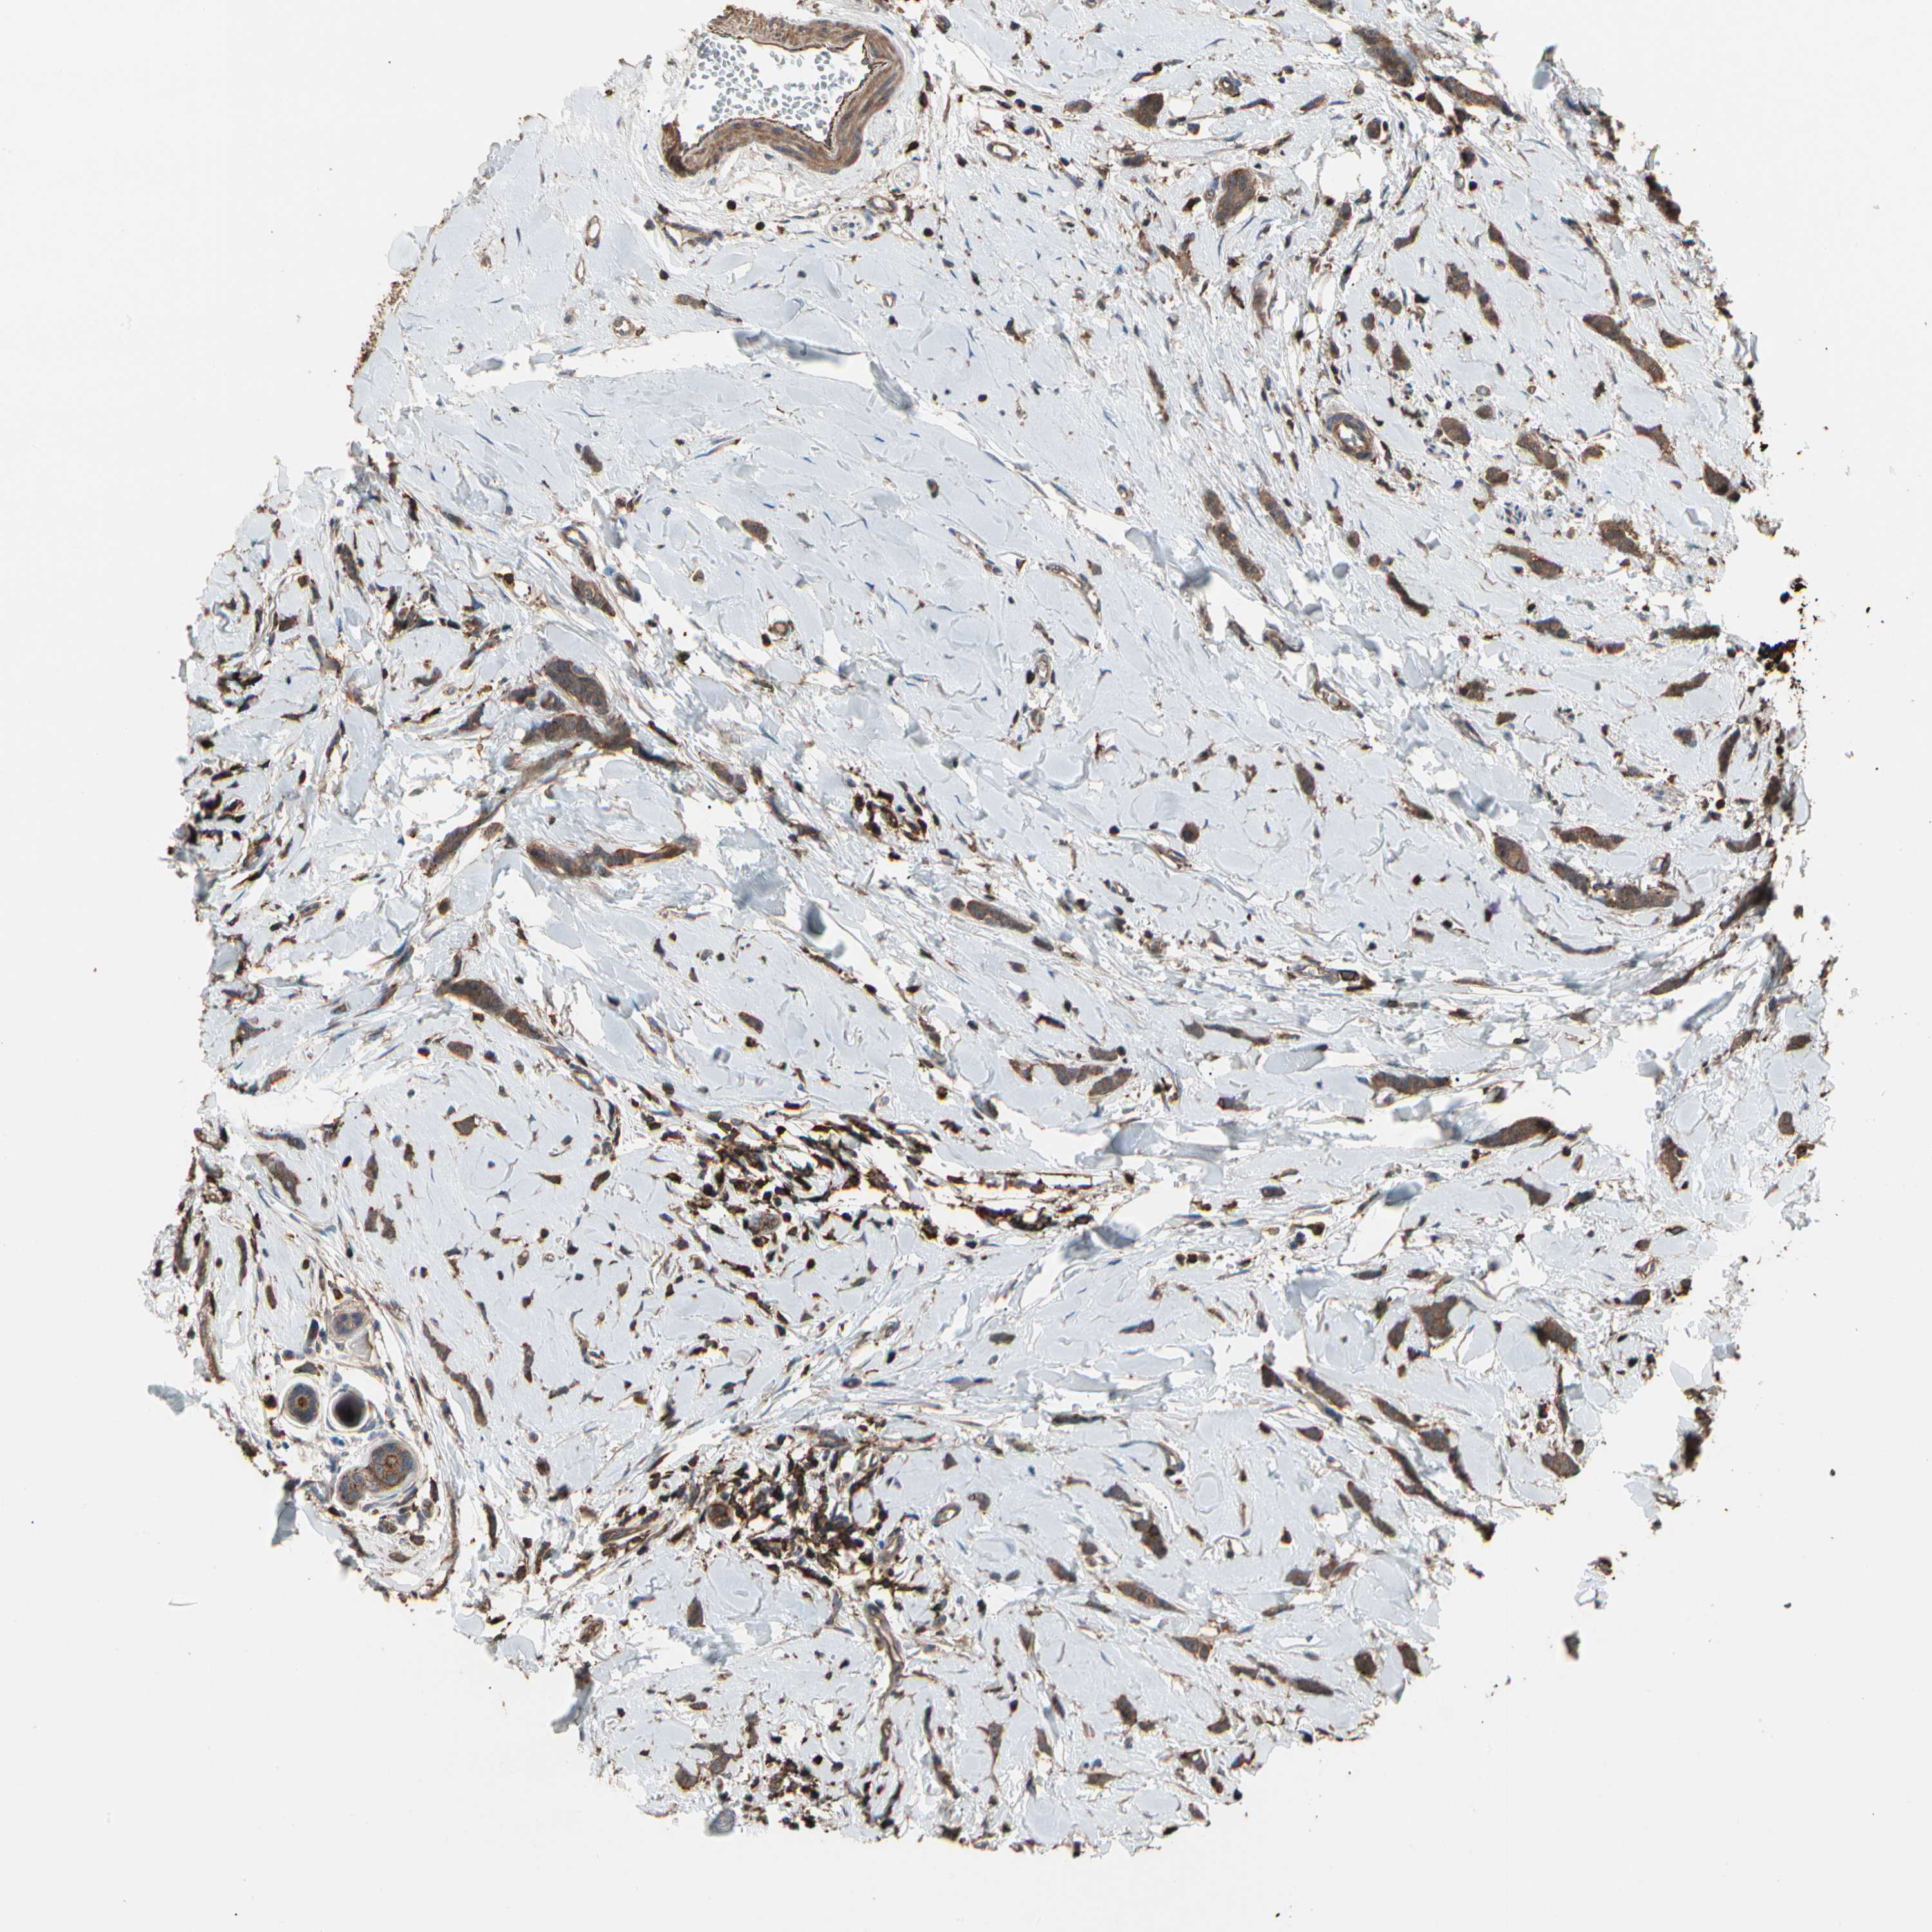

BRCA TCGA BRCA VALIDATION PROTEIN EXPRESSION